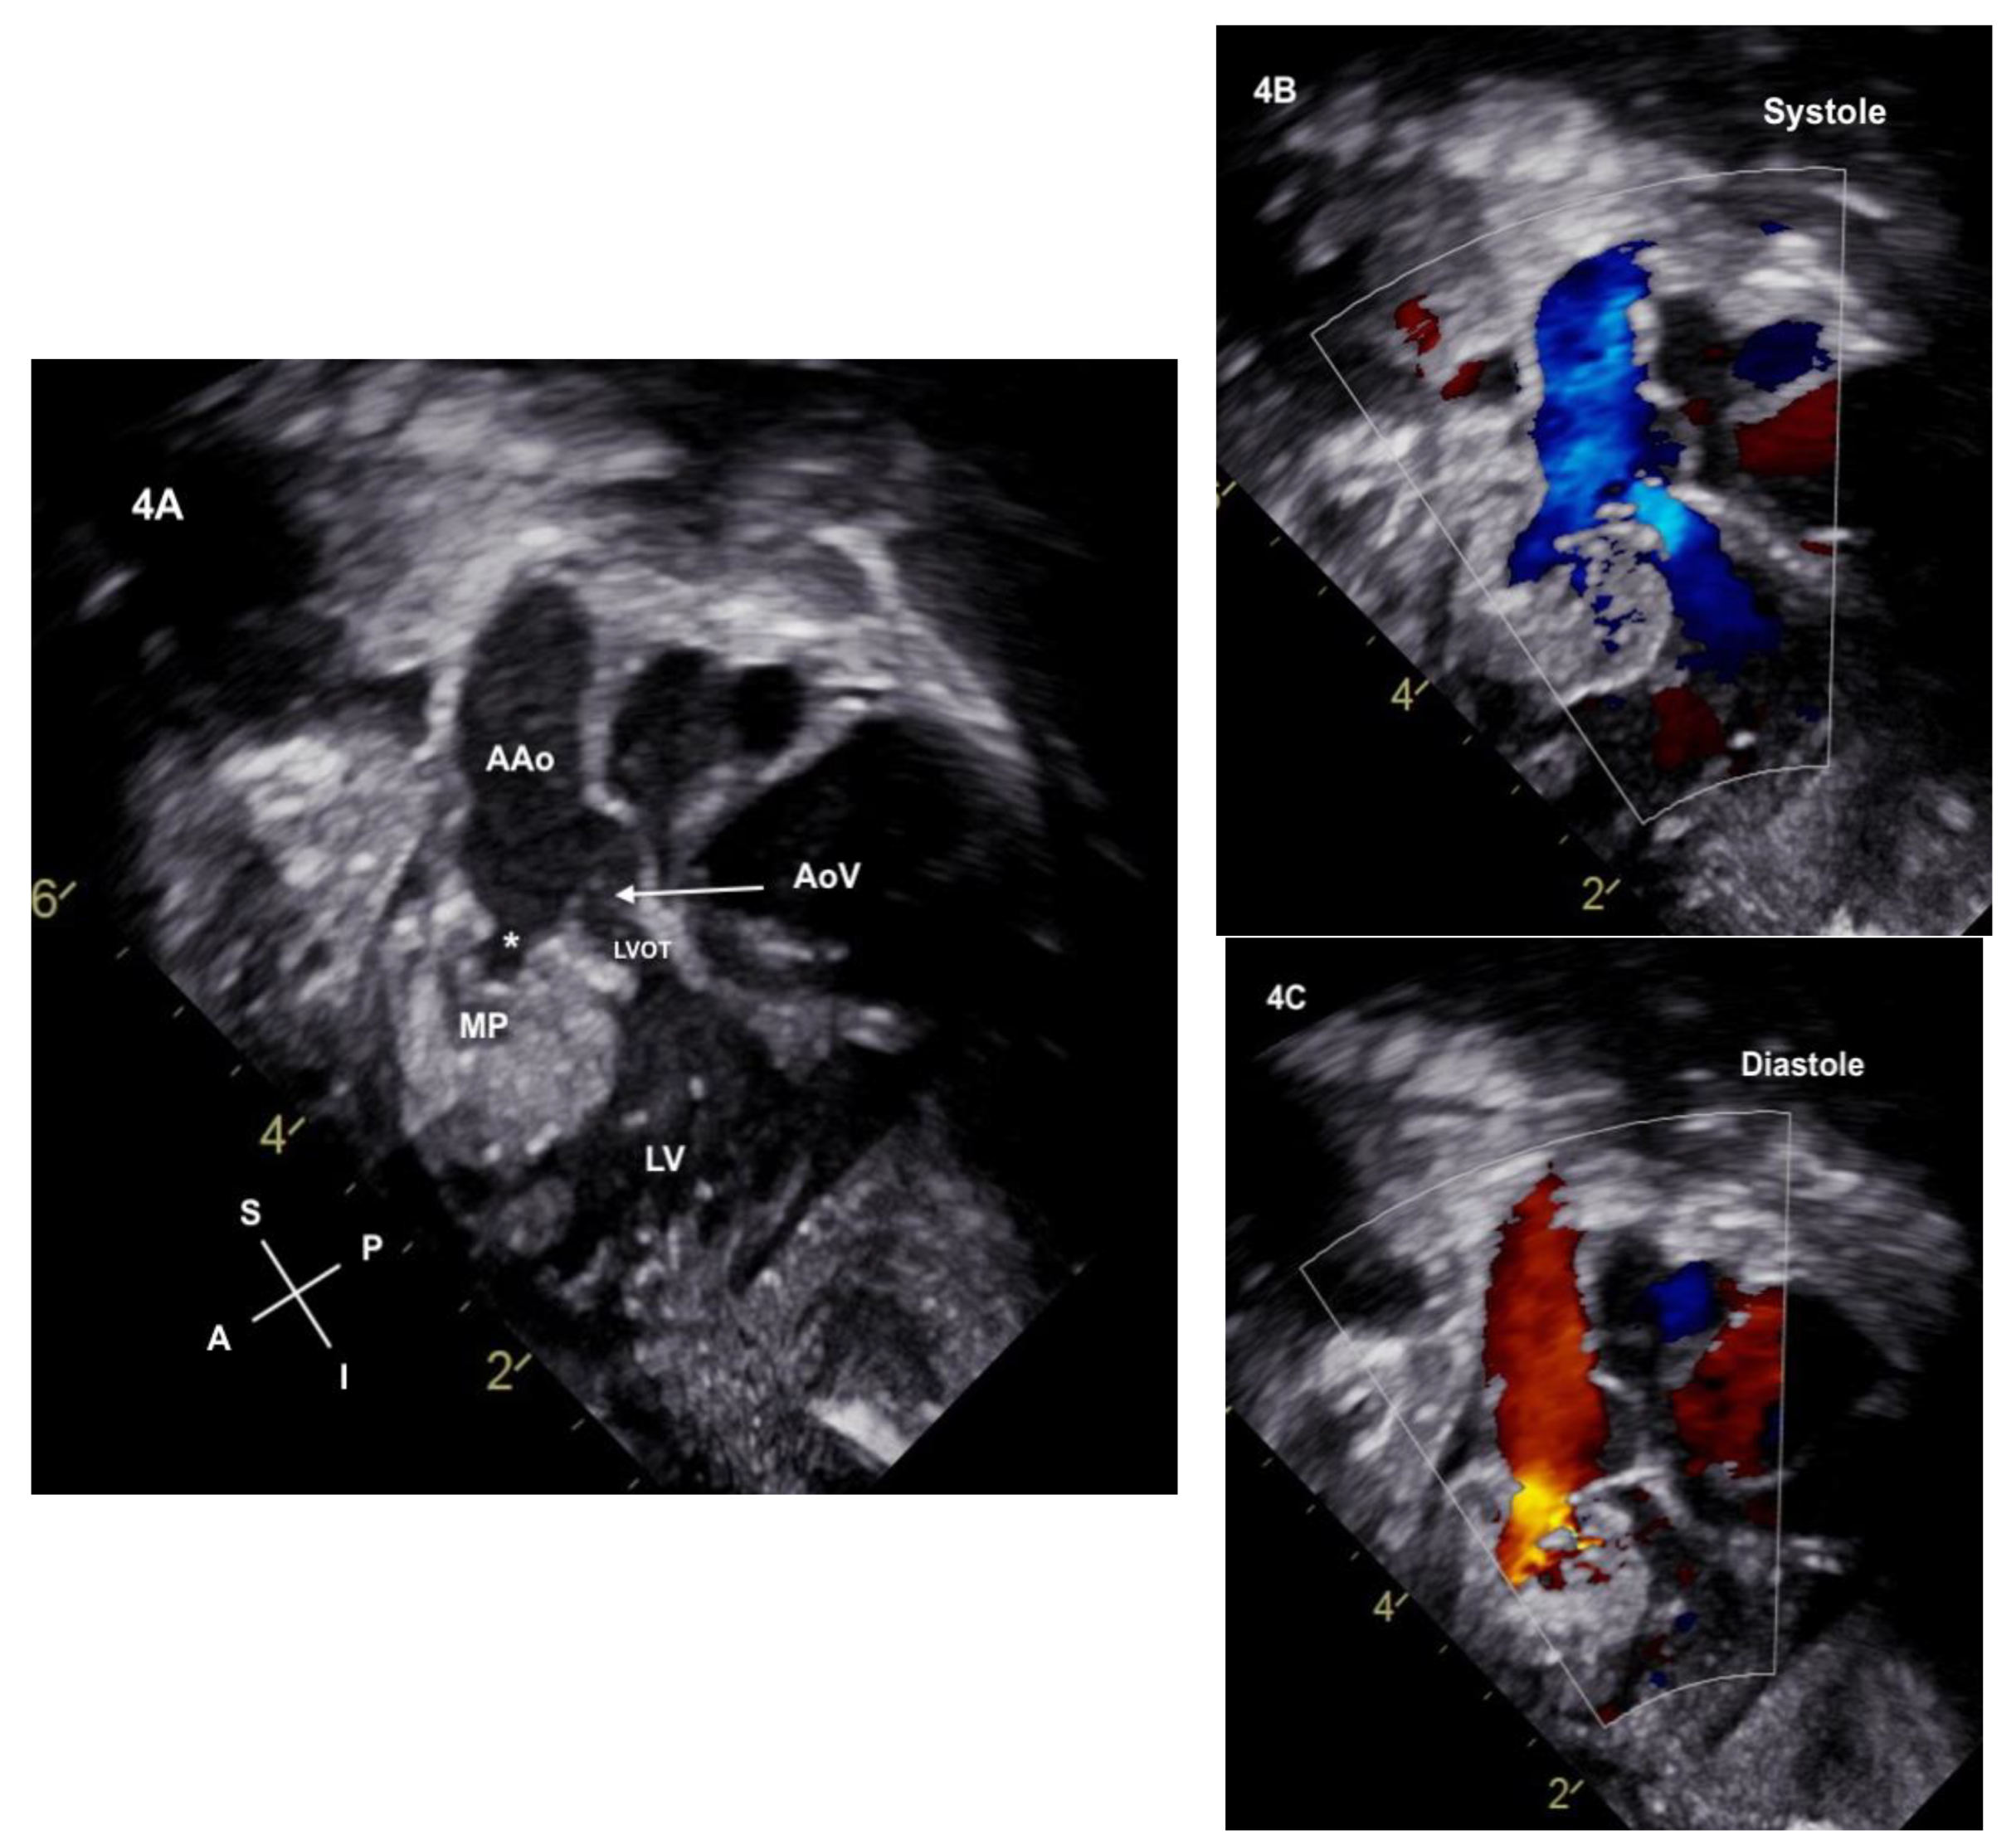

2. Case Description